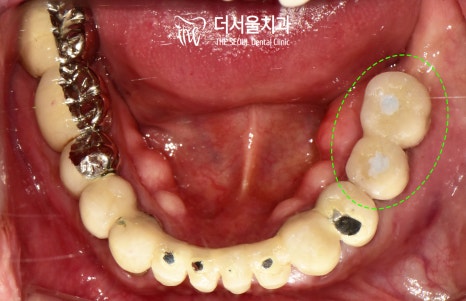

구강을 살펴보면

곳곳에 비어있는 공간이 존재하며

그 자리로 부분 틀니를

사용하고 계셨던 것을 알 수 있습니다.

보통 악당 6개 정도의

인공치근을 식립하는데,

이 케이스에서는 악궁의 크기가 크고

오랜 틀니의 사용으로

치조골이 퇴축되어

적절한 고정력을 얻기 어려운 부위가 있어

7개의 식립을 계획했습니다.